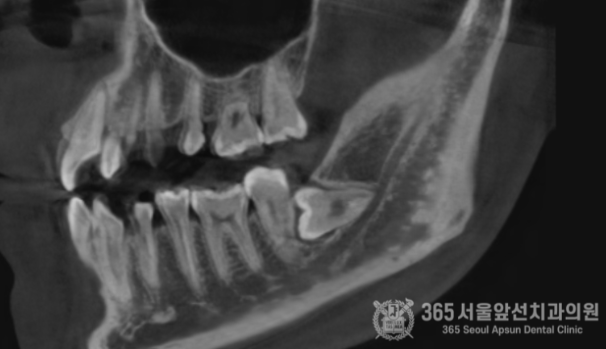

아래턱에 매복사랑니가 있는데, 집근처 동네치과에서 발치가 불가능하다고 대학병원에 가보라고 했어요. 오늘은 완전수평 매복 사랑니의 발치 증례를 소개해드리겠습니다. 집 근처 치과에 방문했다가 완전수평 매복사랑니 발치가 불가능하다는 판정을 받은 환자분께서 내원하셨습니다. 촬영일시 : 2024.05.15. 초진 엑스레이 사진입니다. 완전히 수평으로 매복되어 있으며, 신경관과 뿌리가 겹쳐져 있는 양상이 관찰됩니다. 환자분께선 발치가 불가능할까봐 걱정이 많으셨으나 걱정하지말라고 안심시켜드리고 매복 사랑니 발치를 진행했습니다 ㅎㅎ 촬영일시 : 2024.05.15. 3차원 CT 영상입니다. 뼈 속에 완전히 파묻힌 사랑니를 볼 수 있습니다. 촬영일시 : 2024.05.15. 신경관과 뿌리가 겹쳐져 있는 양상도 관찰됩니다. 조심스럽고 안전한 발치가 필수적이겠습니다. 촬영일시 : 2024.05.15. 발치 후 엑스레이 사진입니다. 발치에 소요된 시간은 총 10분으로 정확하고 빠르게 발치해드렸습니다. 빠르고 정확한 진료를 추구하는 강동우 대표원장이었습니다. 365서울앞선치과의원은 365일 늘 가까운 서울대학교 치과병원을 지향합니다! [ 치료기간: 2024년 5월15일 ] ※ 365서울앞선치과의원의 모든 포스팅은 각 진료과 의료진이 직접 작성합니다. 365서울앞선치과의원 블로그의 임상 케이스 게시물은 환자분께 의학적으로 정확하고 상세한 정보를 드리기 위해 각 진료과 의료진이 직접 작성하며, 모든 증례 사진은 본원 의료진이 직접 시술한 증례를 촬영한 것으로, 의료법 제23조, 제56조에 의거하며 환자분의 동의를 얻어 포스팅에 사용하였습니다. 또한 해당 케이스는 본 환자분의 치료 결과이며, 환자 상태에 따라 치료의 결과는 달라질 수 있습니다. |